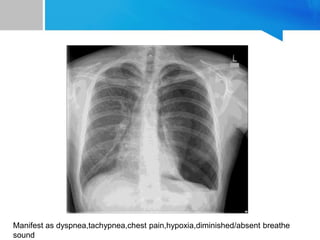

Tension pneumothorax • Etiology-usually traumatic • Pathophysiology Parenchymal tear in lungs act as a one way valve With each inhalation additional air is accumulated without any means of escape Leads to increased intrathoracic pressure with mediastinal content shift to contralateral chest causing decrease in venous return

Manifest as dyspnea,tachypnea,chestpain,hypoxia,diminished/absent breathe sound